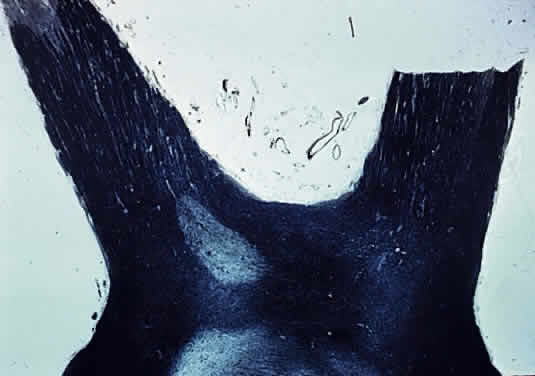

Primary demyelination refers to demyelinating disease of unknown etiology (Figs. 24 and 25). Loss of myelin occurs early but initially the axons are undamaged (disseminated sclerosis, acute disseminating myelitis), so that visual function may return. The damaged myelin is removed by macrophages followed by astrocytic proliferation, which produces a glial scar or plaque (Fig. 26).

Fig. 25. Retrolaminar loss of myelin. Optic nerve from patient with multiple sclerosis (Luxol Fast Blue staining)

Fig. 26. Optic chiasm (Luxol Fast Blue staining). Well-delineated plaque of demyelination. Patient with multiple sclerosis.